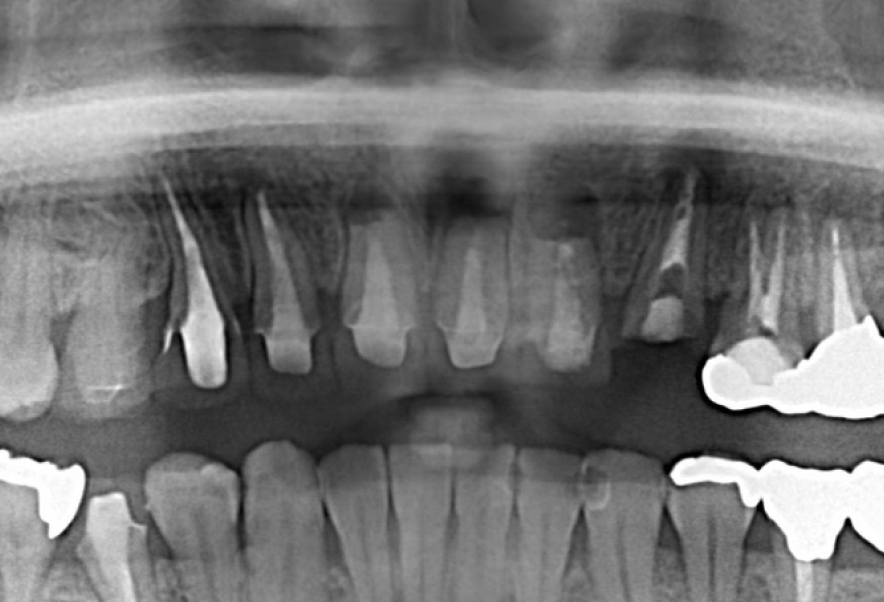

Before

After

他院で抜歯と診断された歯の精密根管治療